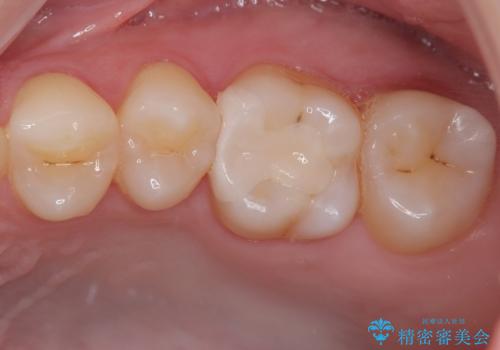

銀歯を気にせずに笑うことができると満足していただきました。